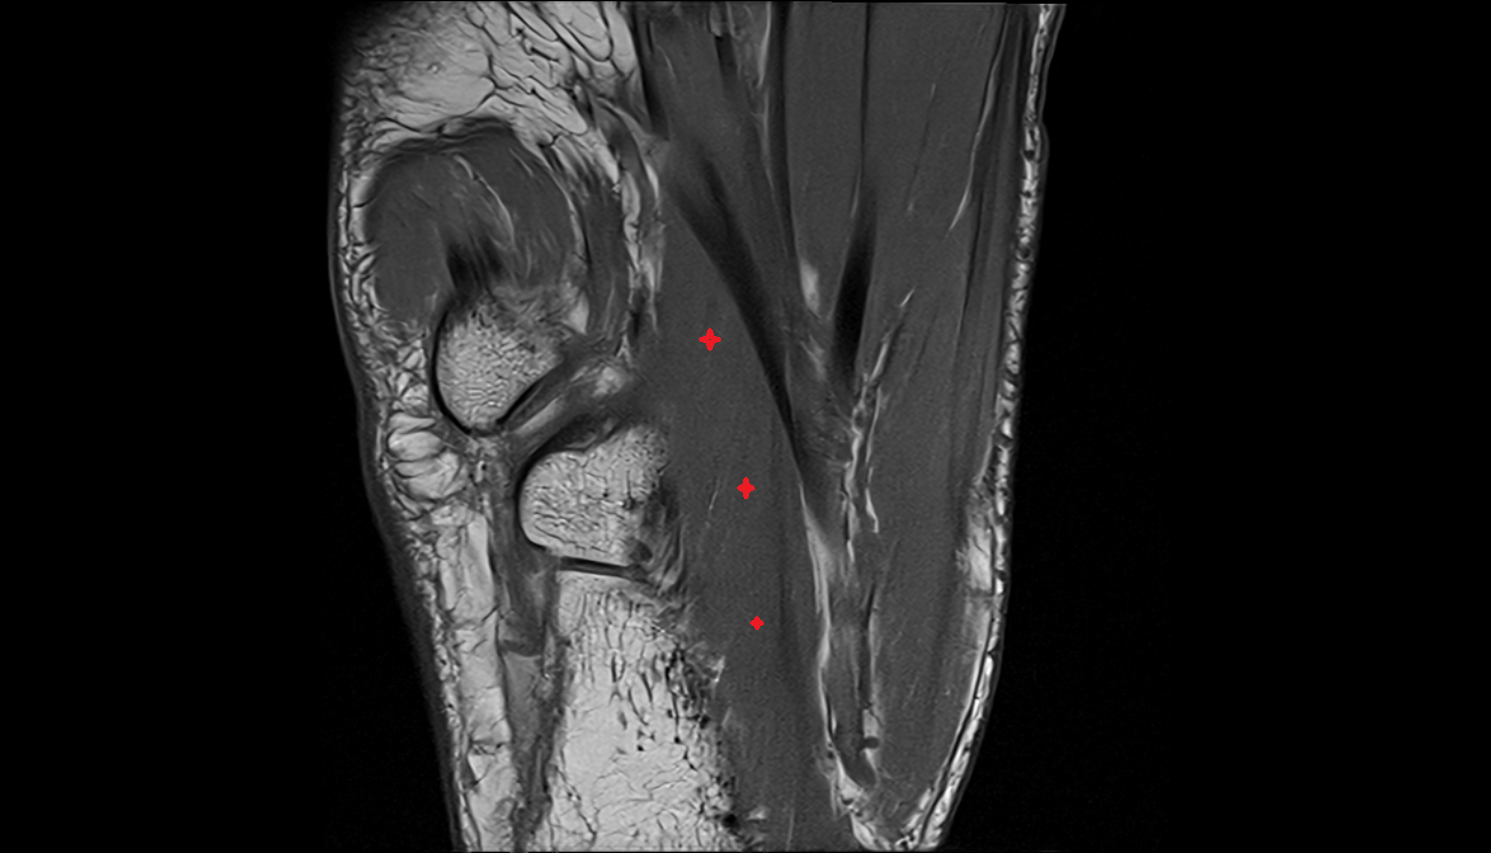

- Talus

- Neck of talus

- Calcaneus

- Sustentaculum tali

- Tibialis posterior tendon

- Flexor digitorum longus tendon

- Flexor hallucis longus tendon

- Achilles tendon

- Flexor retinaculum

- Kager fat pad (pre-Achilles fat pad)

- Inferior calcaneal nerve (Baxter’s nerve)

- Medial plantar nerve

- Lateral plantar nerve

- Posterior tibial artery